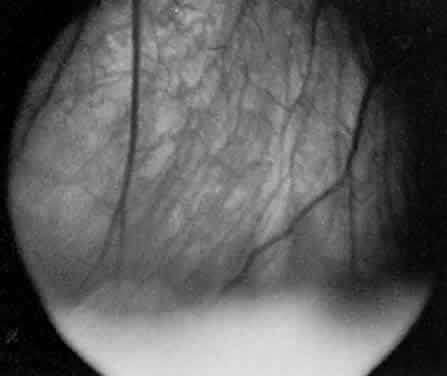

In pars planitis, the inflammatory signs are greatest in the vitreous cavity. The vitreous gel is syneretic and shows varying amount of fibrin, cells, and strands. The hallmark of pars planitis is the presence of exudates in the inferior vitreous base (Fig. 1). In early stages these exudates may appear as discontinuous yellow-white clumps (fluffballs or snowballs). However, as the disease progresses, these exudates may increase in number and size until they coalesce to form a fluffy white exudate over the inferior peripheral retina and pars plana. Later, the exudate organizes into a smooth white fibrous-appearing band. This membrane has been termed a snowbank because of its resemblance to white fluffy snow. The term pars planitis is reserved for intermediate uveitis in which snowbank is present. The amount of vitreous inflammation is usually symmetric in both eyes. However, in some cases, a prominent snowbank may be present in one eye but only a few fluff balls in the other. Scleral indentation is often required to visualize the snowbank (Fig. 2).7,26

Fig. 2. Pars planitis. Scleral depression elevating the snowbank into view with indirect ophthalmoscopy.